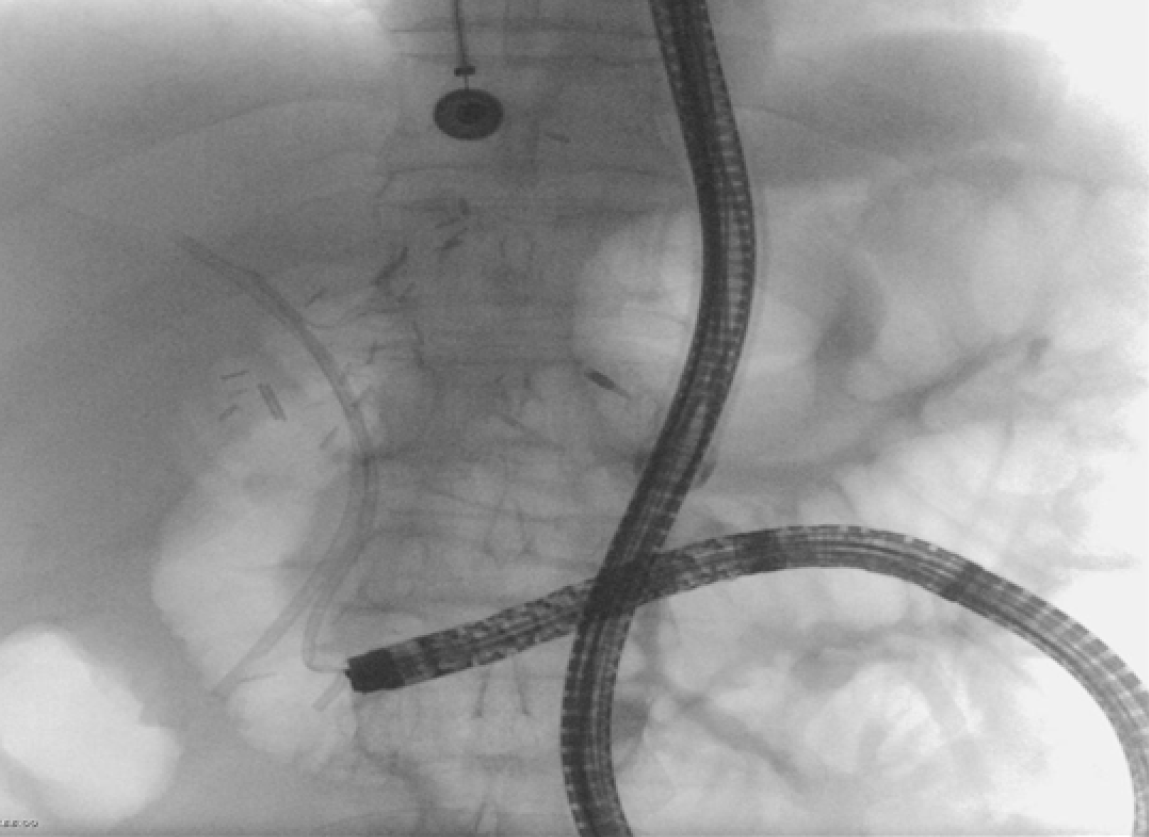

Figure 2

Fluoroscopic image of short-single-balloon enteroscopy assisted endoscopic retrograde cholangiopancreatography in a Roux and Y reconstruction.